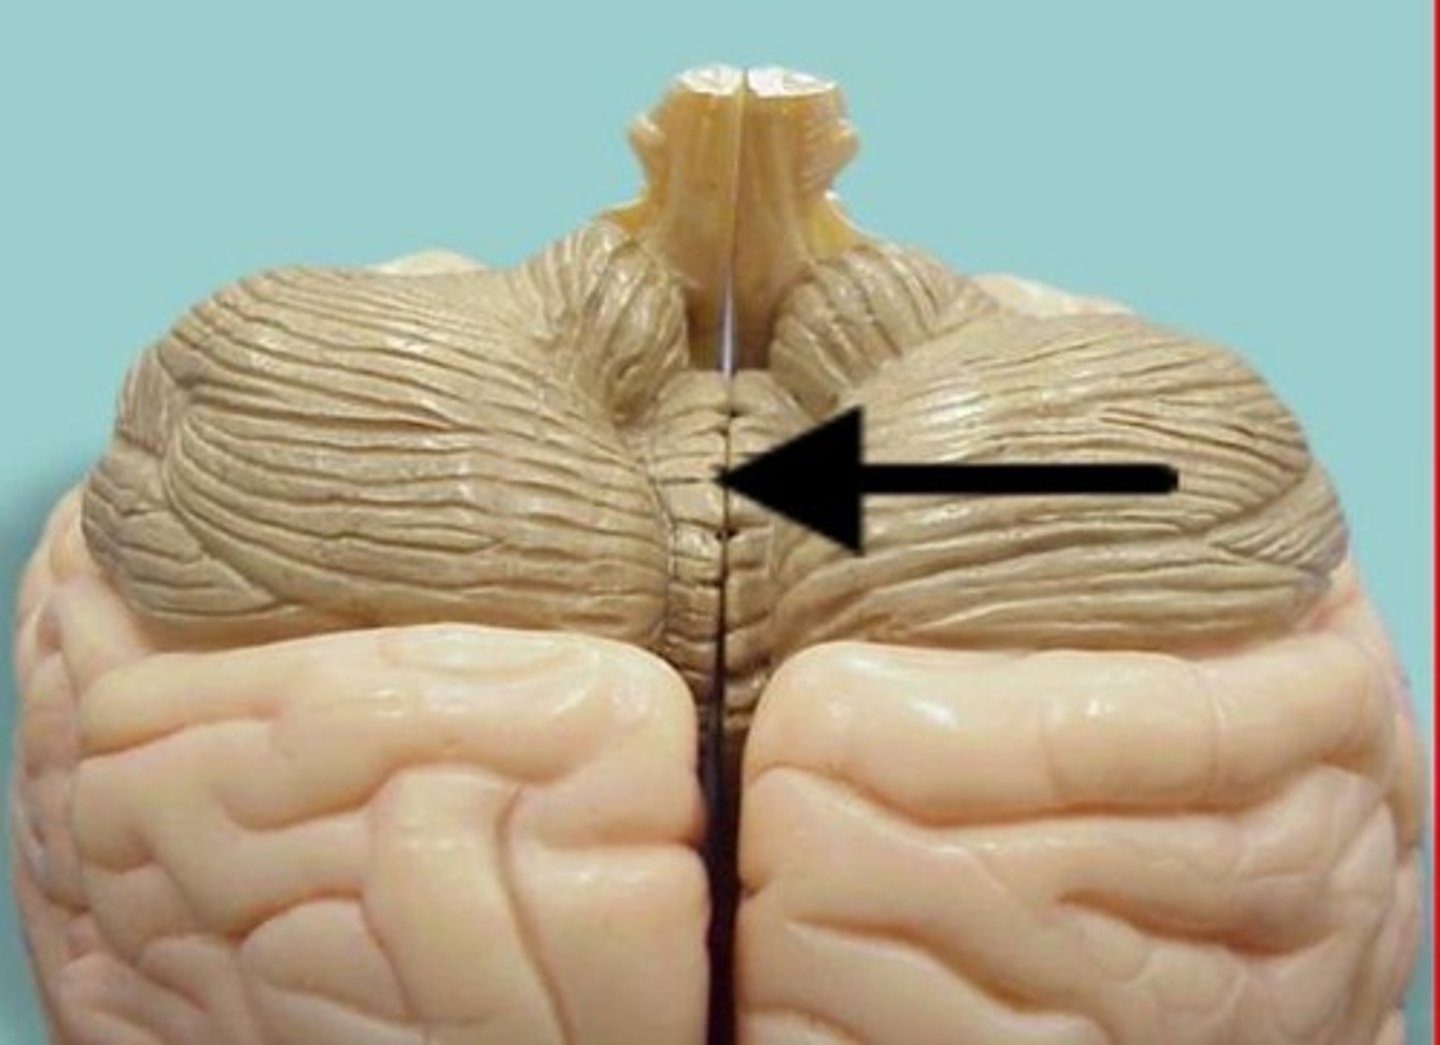

cerebellum

right and left cerebellar hemispheres

vermis

cerebellar cortex

arbor vitae

white matter